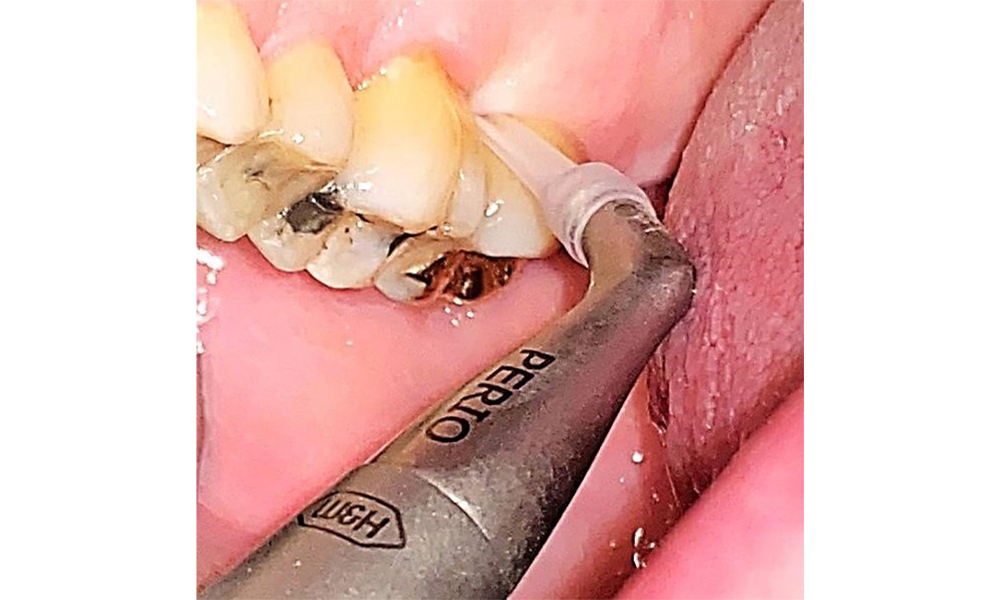

Nu există limitări în ceea ce privește alegerea metodelor de instrumentare. Sunt esențiale intervențiile subgingivale și supragingivale regulate, pentru prevenirea progresiei bolii - datorită parodontozei preexistente și a riscului ridicat de recidivă. Nu există limitări privind alegerea instrumentelor pentru îndepărtarea mecanică a biofilmului dintr-o perspectivă medicală generală, iar îndepărtarea trebuie efectuată în funcție de necesități. Placa dură și mineralizată, cum ar fi tartrul și concrețiunile, trebuie îndepărtate cu ajutorul pieselor de detartraj manuale sau al scalerului sonic/ultrasonic (Fig. 9) (8, 9).

Îndepărtarea biofilmului supra și subgingival este indispensabilă pentru conservarea stabilității situației parodontale. Folosirea air-flow-ului cu pudre slab abrazive este oportună în acest scop. Pungile parodontale și suprafețele radiculare expuse trebuie igienizate cu ajutorul pudrelor slab abrazive. Utilizarea unei anse parodontale flexibile este recomandată pacienților cu profunzimi de sondare crescute (mai adânci de 5 mm) (fig. 10). (9)

Adâncimea pungilor de până la 5 mm poate fi, de asemenea, gestionată utilizând o ansă convențională (9). Se recomandă, de asemenea, utilizarea unui air-flow cu pudră slab abrazivă, pentru marginile restaurărilor, zonele interdentare și fisuri. Lustruirea rotativă (fig. 11) uniformizează ușor suprafețele dentare, ceea ce, la rândul său, contribuie la încheierea optimă a tratamentelor dentare profilactice, reducând readeziunea bacteriană (10).